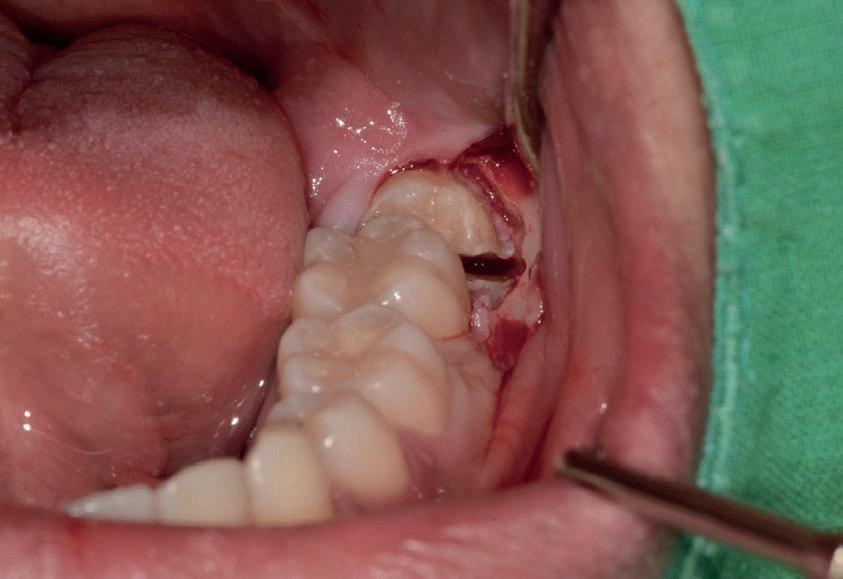

Abbiamo estratto il dente del giudizio inferiore di destra in una paziente di 22 anni, un’amica, utilizzando il manipolo dritto, con il proposito di fare delle foto dell’intervento. Figg. 173-179

Dalla radiografia (Fig. 166) sembrava che il dente avesse due radici separate, quindi è stato eseguito un taglio orizzontale utilizzando il manipolo dritto per sezionare il dente a metà. Tuttavia, la corona si è frat-

turata poiché in realtà le radici erano unite e il dente non è stato sezionato completamente.

Bisogna prendere in considerazione sempre molti fattori come, ad esempio, la forma delle radici, il sottosquadro nella regione distale del secondo molare e l’osso alveolare disto-vestibolare. Se necessario la corona e le radici vengono separate intenzionalmente per estrarre il dente, proprio come in questo caso.

Figg. 173-179 - Caso 3: tecnica di estrazione con divisione orizzontale utilizzando il manipolo dritto. Fig. 173 Fig. 174 Fig. 175 Fig. 176 Fig. 177 Fig. 178 Fig. 179